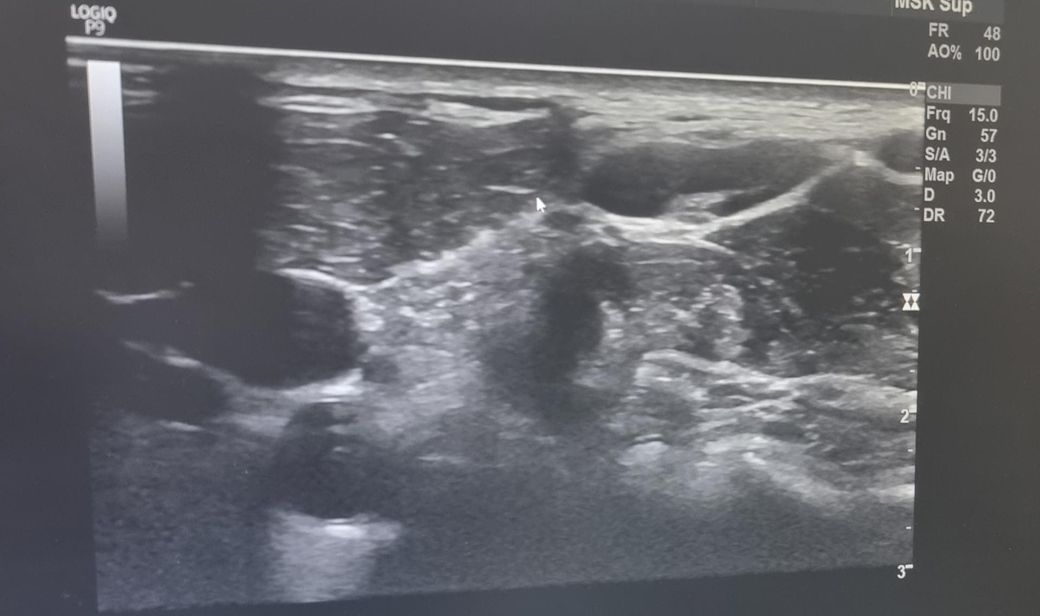

한 달 넘게 멍울 만져져서 초음파 받았는데 크기가 좀 커서요 괜찮나요? 궁금합니다 ㅜㅜ V5 구역입니다.

초음파 사진 괜찮나요 ㅜㅜ?